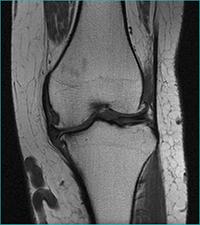

MRI scanners are particularly well suited to image the non-bony parts or soft tissues of the body. They differ from computed tomography (CT), in that they do not use the damaging ionizing radiation of x-rays. The brain, spinal cord and nerves, as well as muscles, ligaments, and tendons are seen much more clearly with MRI than with regular x-rays and CT; for this reason MRI is often used to image knee and shoulder injuries.